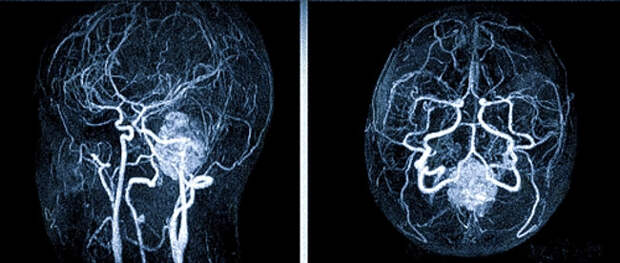

Магнитно-резонансная томография (МРТ) является высокоинформативным методом диагностики заболеваний центральной нервной системы. МРТ позволяет визуализировать не только структуры головного мозга, но и кровеносные сосуды, включая интракраниальные вены.

Показаниями к проведению МРТ интракраниальных вен являются подозрение на тромбоз синусов твердой мозговой оболочки, артериовенозную мальформацию, сосудистые аномалии развития, а также оценка состояния сосудов после нейрохирургических вмешательств или травм головы.

Преимущества метода заключаются в высокой точности изображения, отсутствии лучевой нагрузки и необходимости использования контрастных веществ при исследовании венозного русла. Результаты МРТ позволяют врачам получить детальную информацию о состоянии вен головного мозга, что способствует точной диагностике патологических изменений и выбору оптимальной тактики лечения пациентов.